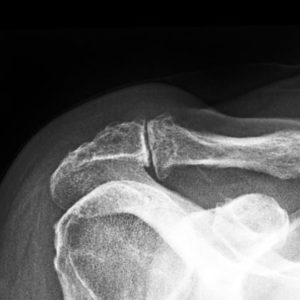

Anatomie van het acromio-claviculair gewricht AC-gewricht met arthrose - kraakbeenslijtage

Op basis van het verhaal is er vaak al een sterk vermoeden van de diagnose. Bij klinisch onderzoek van de arts is het gewrichtje meestal sterk drukgevoelig. Ook specifieke testen zijn pijnlijk. Klassieke radiografie geeft een idee van de graad van slijtage en de grootte van de papegaaienbekken. Arthro-Ct scan gebeurt soms om ook andere bronnen van schouder pijn op te sporen. Soms is een botscan nodig om de correcte diagnose te kunnen stellen (bv. indien er ook nek afwijkingen aanwezig zijn).

Klinische test voor AC-gewrichtsartrose Röntgenfoto van AC-artrose